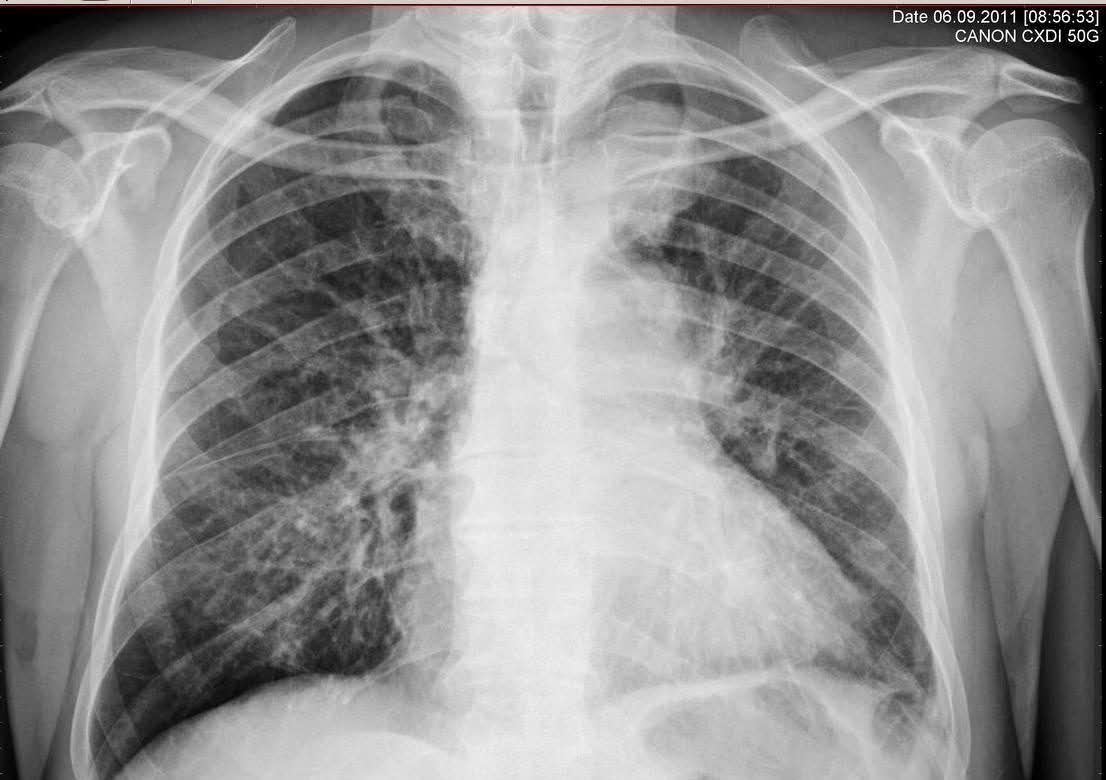

很多女性在进行胸部 x 光或 ct 检查后,会被告知存在肺纹理增多的

肺纹理增多严重吗?是什么病?怎么办?医生帮你解答清楚

"肺纹理增多",是一种什么病?会不会很严重?医生详解